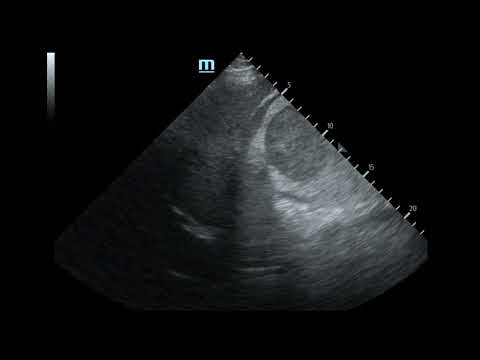

Massive Traumatic Retroperitoneal Hematoma, US 1 Unannotated